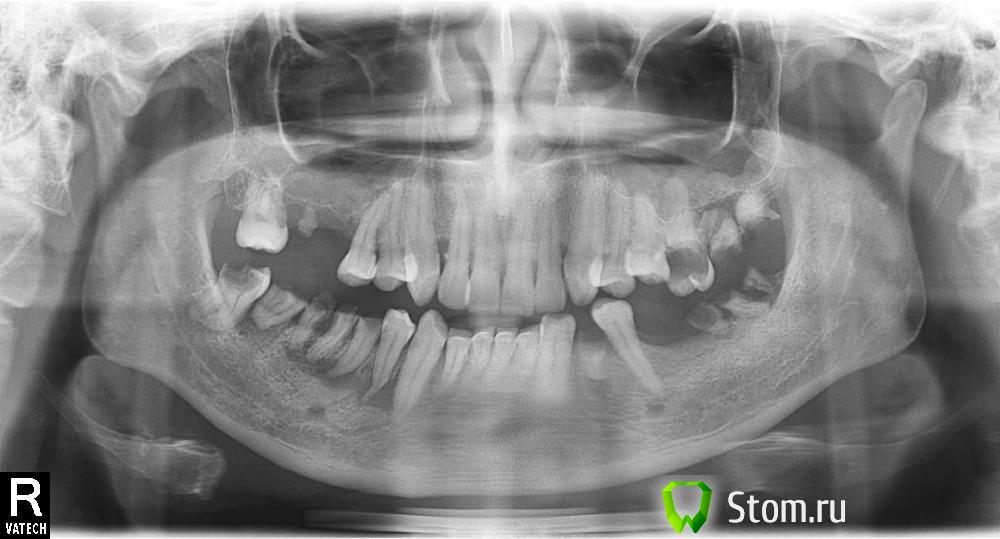

kzn Опубликовано 22 ноября, 2011 Поделиться Опубликовано 22 ноября, 2011 После 15 лет решил заняться зубами. Снимок прикрепляю ниже. Опишу ситуацию. Врач прошла каналы трёх зубов, на нижней восьмёрке всё уже доделали и стоит пломба нормальная. Лечение было безболезненным. С верхней 6 ( помоему, на картинке справа торчит) сточили, поставили временную и после этого обнаружилось, что там что-то не так с корнем ( делали местный снимок ) он не в кости оказался м пока не пломбируем. Все лечения связаны с тем, чтобы потом поставить металлокерамику или имплантаты. Завтра идти на удаление! Жесть! Не знаю почему но мне кажется это болезненно. Почему так думаю? Потому, как сегодня убирали зубные камни и это реально было больно, хоть анестезию и делали нормально. У сеня вопросы: 1) Мне сказали что нужно удалять 7 зубов, как Вы считаете это так?2) Почему было больно при удаении камней с анестезией? Может это сама по себе процедура белезненная?3) Что делать с верхней шестёркой, сохранять или как?4) Ставить импланты или металлокерамику.5) Вреден ли ультракаин, его мне кололи два дня подряд, сегодня двойная доза была.6) Стоит ли завтра удалять зубы. Я буду ходить в стоматологию третий день подряд. Может это большая нагрузка на орагнизм, как анестезии , так и психологически.7) Действительно ли уколы это самое болезненное в современной стоматологии? Спасибо всем, заранее. Ссылка на комментарий

Doc Опубликовано 22 ноября, 2011 Поделиться Опубликовано 22 ноября, 2011 1.Смотря что считать. Если корни тоже считать, то там еще больше получается.2. Откуда мы можем знать? Нас там не было. Нет, при проведенной адекватной анестезии не должна.3. Данных маловато, но скорее нет, чем да.4. Импланты и металлокерамика не пишутся через "или". Это разные этапы одного и того же процесса. В Вашем случае если не использовать имплантацию, то будет съемный протез и сверху и снизу5. Нет, не вреден.6. Психологически это Вам решать. С остальных сторон люди месяцами ходят и ничего.7. Так должно быть. Но далеко не всегда, не везде и не у всех получается. Ссылка на комментарий

Doc Опубликовано 22 ноября, 2011 Поделиться Опубликовано 22 ноября, 2011 Не факт, что виноваты руки. Возможна куча причин, в частности индивидуальная непереносимость препаратов, прием алкоголя накануне, стрессовое состояние с выделением больших доз адреналина и многое другое. Не нужно все сразу сводить к кривым рукам. Потому я и написал, что мы точно указать причину не можем.По количеству можно посчитать только после того, как будет ясно сколько зубов уйдет и сколько останется. Однако, думаю, что в любом случае меньше трех наверху, а внизу четырех-пяти имплантатов у Вас не получится, даже если в боковых отделах строить сплошные мосты.Спасти то, что осталось, не проведя грамотного восстановления жевательной эффективности, не получится. Со временем зубы разъедутся во всех направлениях, может нарушиться работа височнонижнечелюстного сустава (а это дорога в один конец, потом вылечить очень сложно!) и будет еще сложнее что-то исправить. Если нет денег на имплантацию, то сделайте хотя бы съемные протезы. Жевать ими не так удобно и жить с ними не так приятно, как с имплантатами, но по крайней мере временно предотвратят деформацию. Ссылка на комментарий